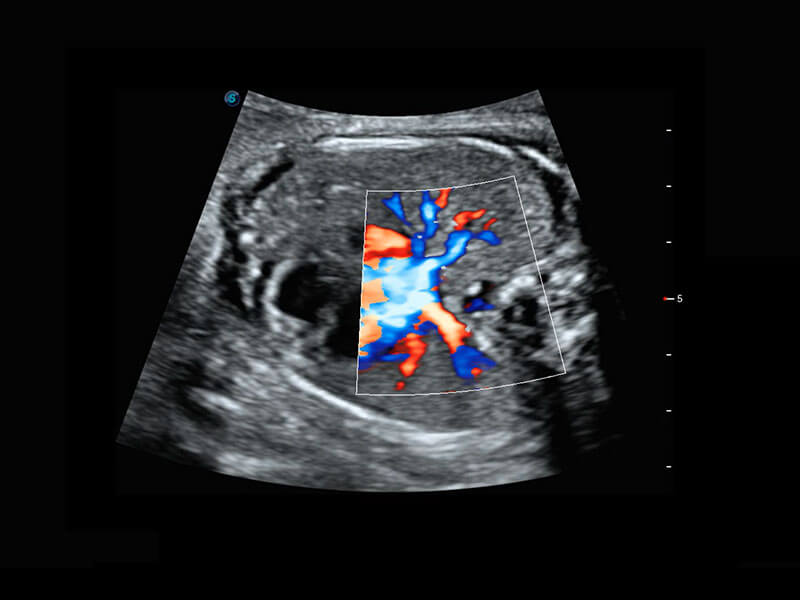

早孕-胎心

高分辨率容积成像-早孕胎儿

胎儿体循环

光影成像-孕囊